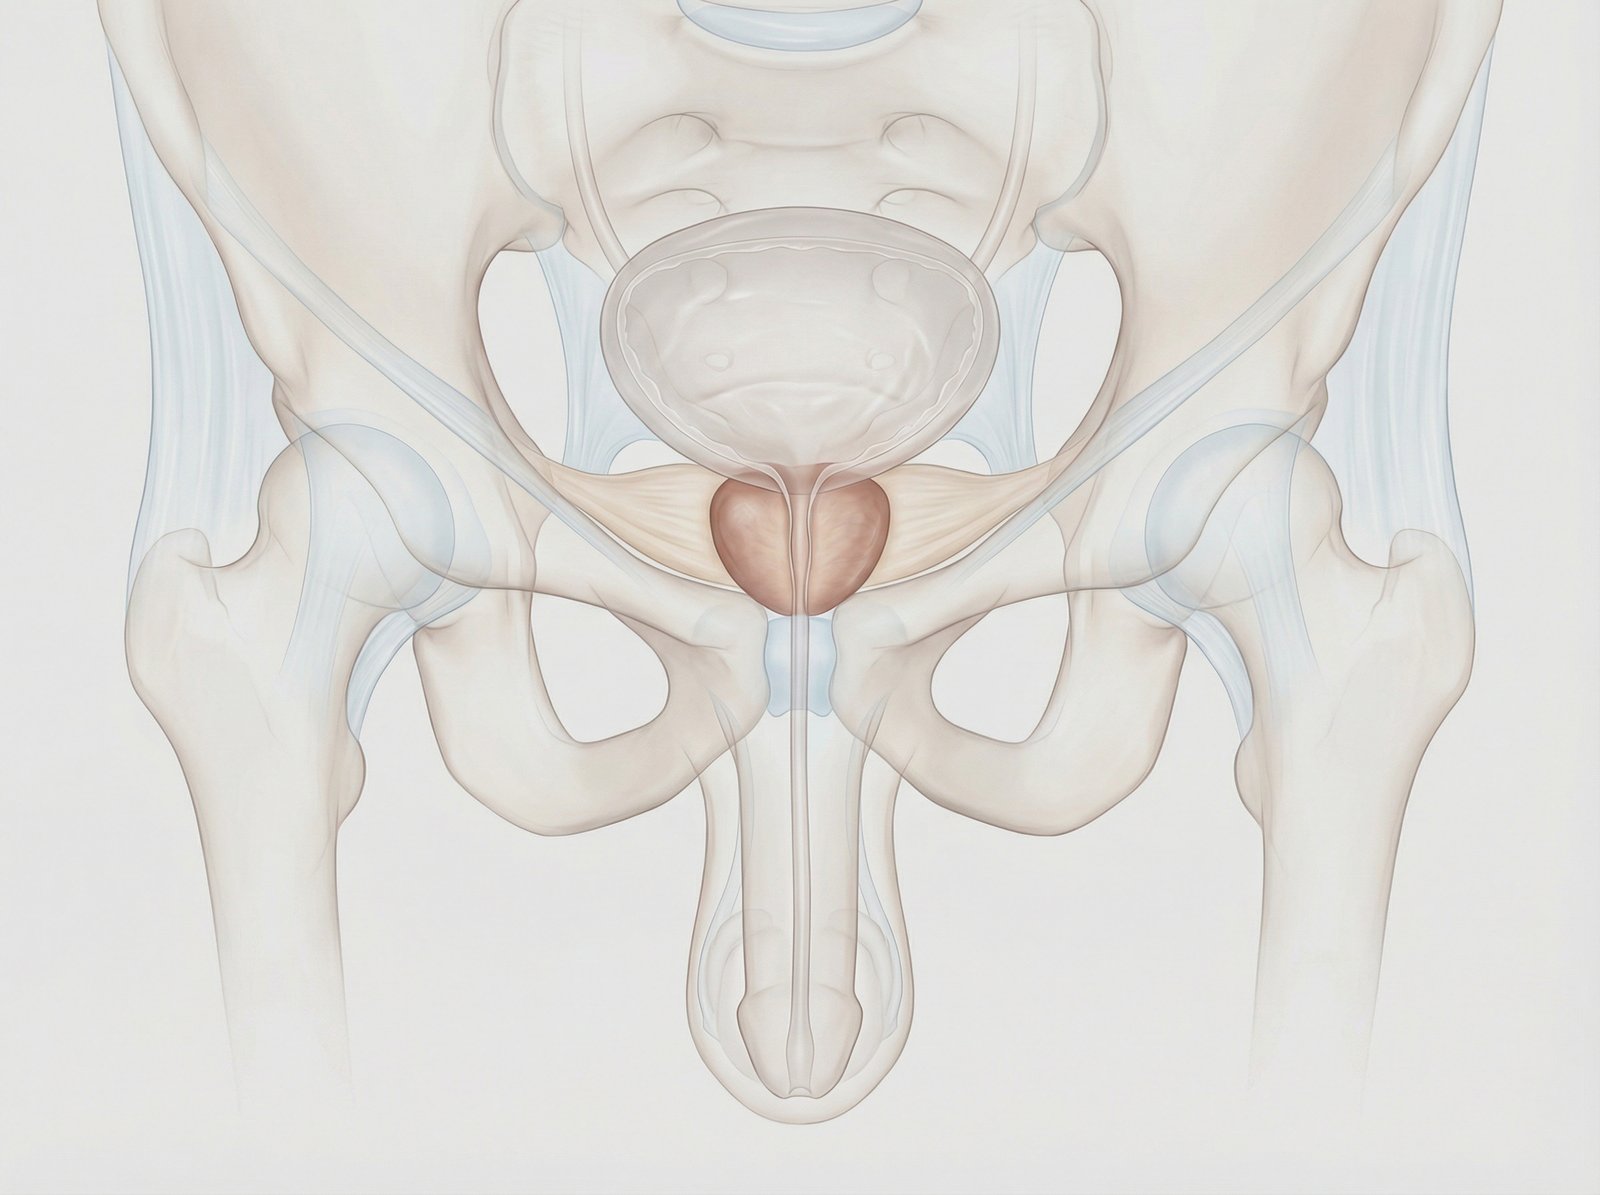

Enucleazione laser a fibra di tulio della prostata (ThuFLEP). Tecnica avanzata e mininvasiva per il trattamento dell’ipertrofia prostatica benigna, che consente la rimozione precisa del tessuto in eccesso con minimo sanguinamento. Recupero più rapido, maggiore sicurezza e miglioramento significativo dei sintomi urinari, per una migliore qualità della vita.

Hai problemi ad urinare a causa dell’ingrossamento della prostata? Presso la clinica Fabjan in Slovenia eseguiamo l’enucleazione laser della prostata con il laser a fibra di Thulium – ThuFLEP.